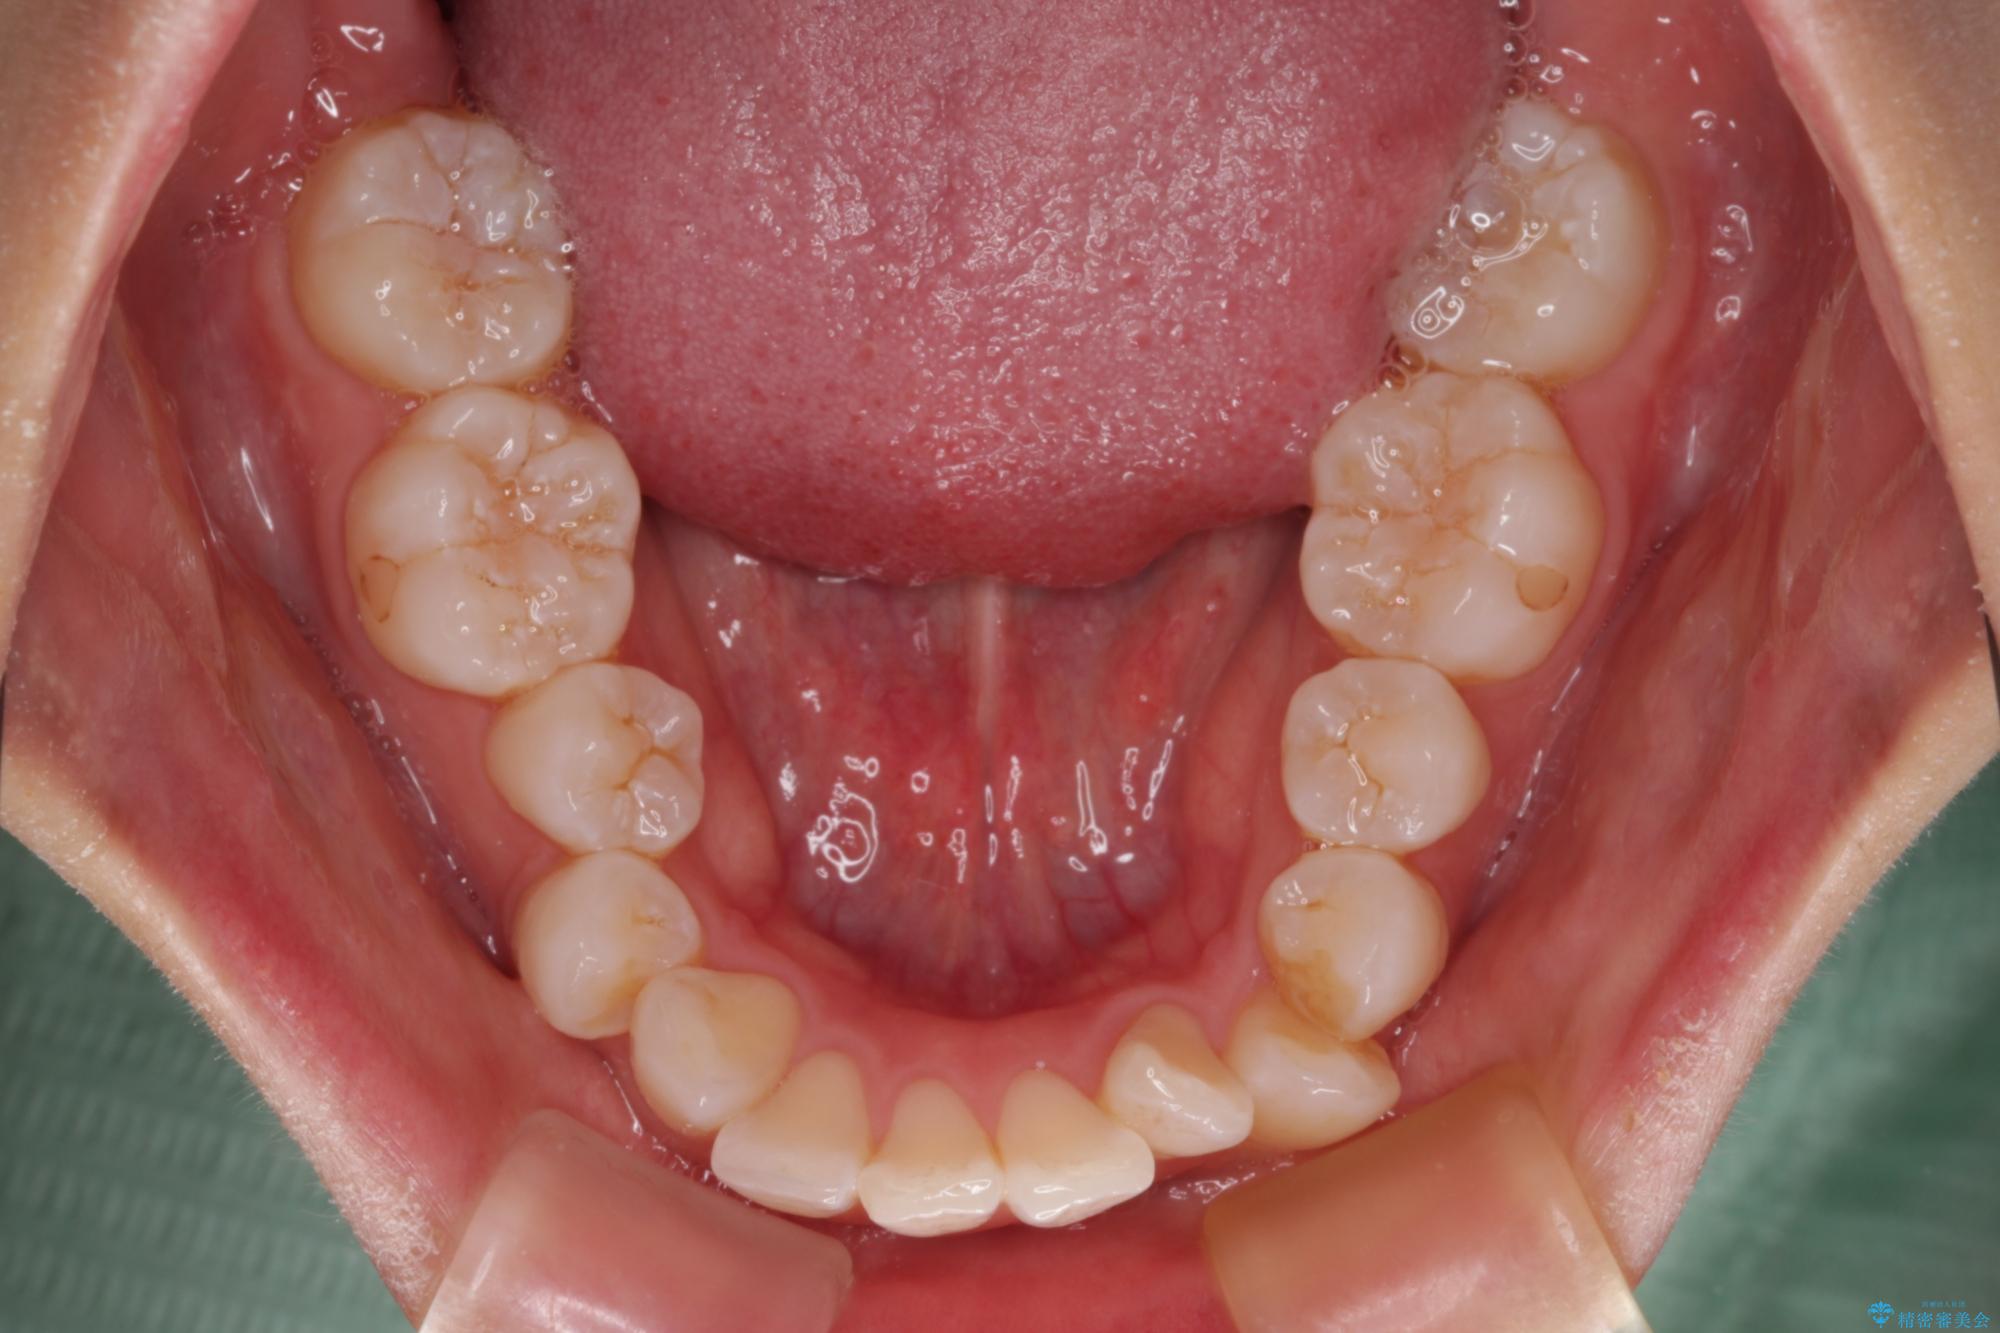

- 口を閉じたときに飛び出してしまう上顎前歯を気にして来院された患者様です。

下顎はデコボコが気になっていたため、上下左右第一小臼歯4本を抜去して、ワイヤー装置にて口元の突出感を改善するよう矯正治療を行うこととしました。